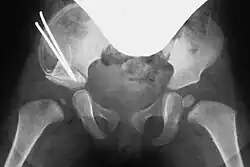

In both techniques, a suitably shaped bone wedge is inserted into the resulting gap under X-ray guidance. If needed, the wedge can be fixed with an osteosynthesis wire (Kirschner wire). The procedure typically takes 45 to 60 minutes for an experienced surgeon.[3][11]

Post-surgery, a pelvic spica cast (modified Fettweiss cast) or abduction orthosis is applied to keep the femoral head centered in the acetabulum during healing. Anesthesia is discontinued afterward.[7]